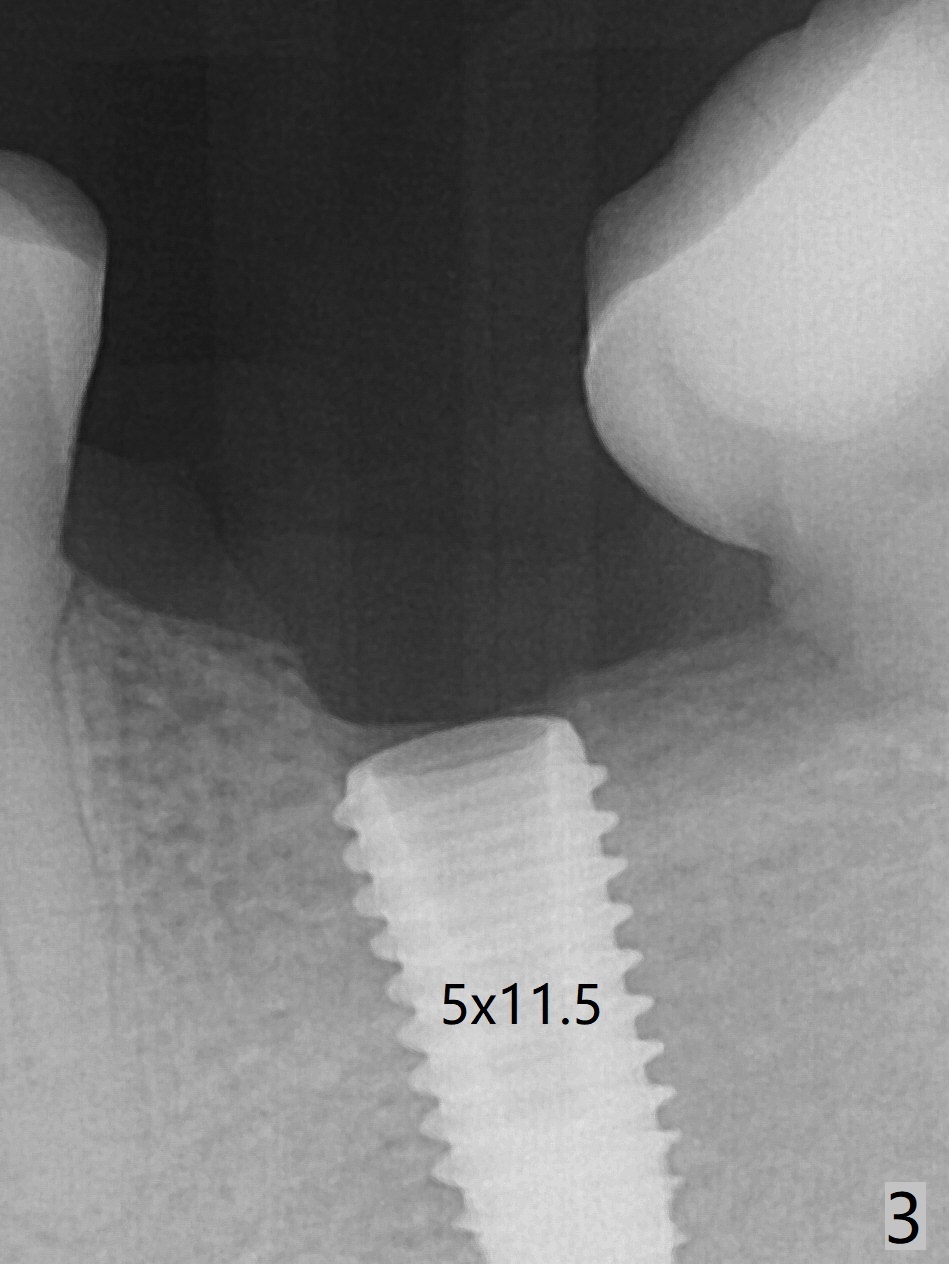

It is difficult to identify the Inferior Alveolar Canal when the initial osteotomy depth is 11.5 mm (Fig.2). Following sequential osteotomy (last drills 4.5x11.5 and 4x13 mm), a 5x11.5 mm implant is placed with >50 Ncm (Fig.3,4). Later the implant is placed .5 mm deeper with placement of a 6.5x4(4) mm abutment and autogenous bone lingually, in which ~.5 mm implant is uncovered. There is mild bone loss distal 6.5 months postop (Fig.5). Before cementation, the crown at #29 becomes loose. The abutment screw needs retightening 6 months post cementation. Six months post retightening, the abutment screw is loose at #14.